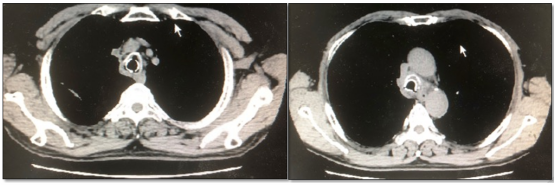

图片

我们研究发现,在全脸面罩下,如果无创通气患者出现了PaCO2升高或气道分泌物引流障碍,可以通过气管镜进行分泌物吸除。镇痛镇静及分泌物引流障碍不是无创通气的绝对禁忌证。可以通过气道管理手段恢复气道通畅,部分患者可以避免插管。

注:a为无创全脸面罩;b为气管镜经全脸面罩进入气道;C为电子支气管镜

国外也有很多无创机械通气期间通过全脸面罩、鼻罩等进行支气管镜检查的报道。对于氧合较差的危重患者,无法耐受气管镜检查,或只能通过气管插管才可进行气管镜检查,也可以用无创通气进行气管镜检查过程中的呼吸支持。